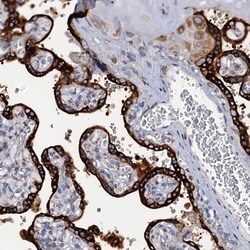

Supportive validation

- Submitted by

- Invitrogen Antibodies (provider)

- Main image

- Experimental details

- Immunohistochemical analysis of KDELC2 in human placenta using KDELC2 Polyclonal Antibody (Product # PA5-58942) shows strong cytoplasmic positivity in trophoblastic cells.